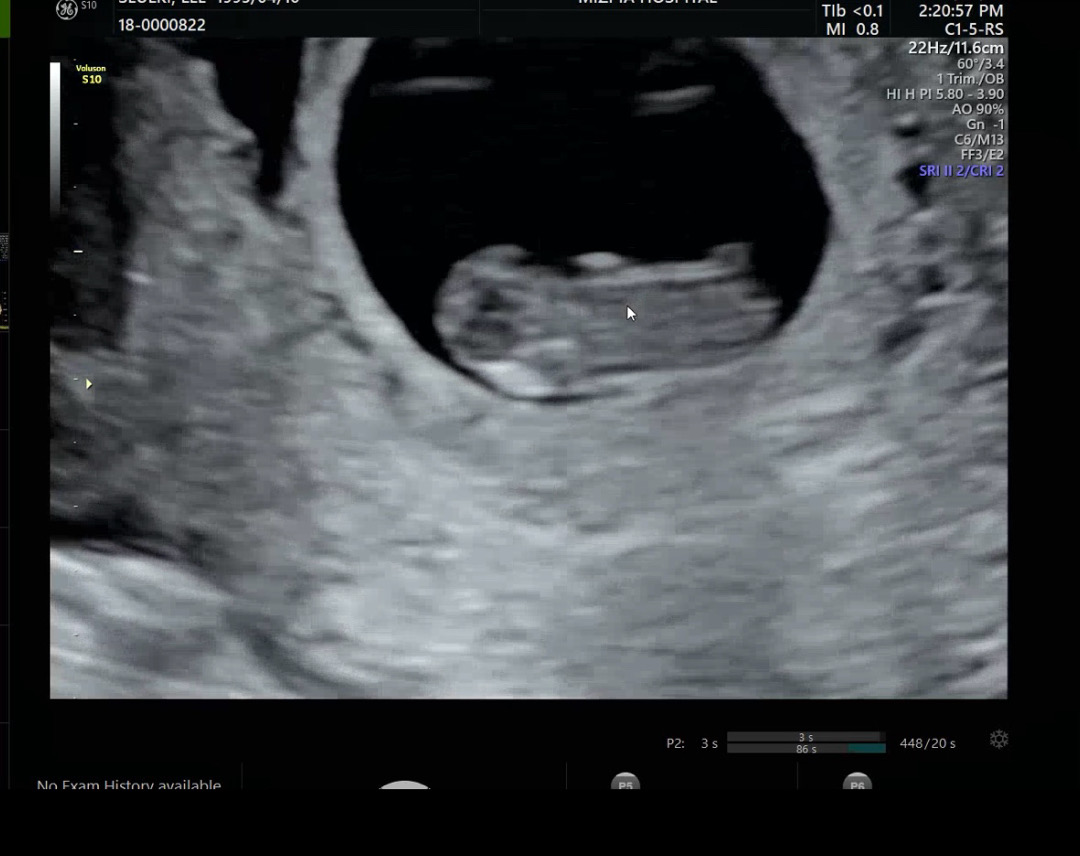

9주0일!! 넘 가만히 있어서 심장소리 들을때까지 잘못된줄알고 엄청 놀랬네요🥹 다행히 마지막에 꼬물꼬물 움직이긴했어요! 다들 초코우유 드시고 가시던데 효과있나용ㅎㅎ??????